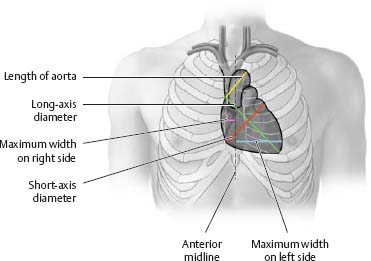

Fig. 7.20 Cardiac borders and configurations

|

Table 7.5 Borders of the heart |

Border |

Defining structures |

Right cardiac border |

Right atrium |

Superior vena cava |

Apex |

Left ventricle |

Left cardiac border |

Aortic arch (“aortic knob”) |

Pulmonary trunk |

Left atrium |

Inferior cardiac border |

Right ventricle |